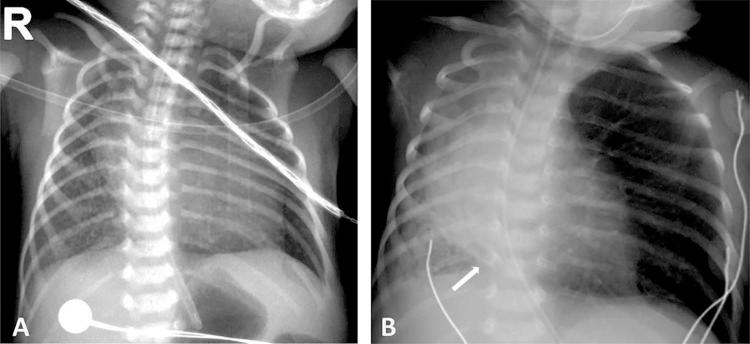

Esophageal lung is a rare communicating bronchopulmonary foregut malformation in which the main bronchus arising from the trachea is absent. The affected lung is usually hypoplastic and aerated via an anomalous airway originating from the esophagus. Other anomalies such as esophageal atresia with tracheoesophageal fistula or VACTERL (vertebral defects, anal atresia, cardiac defects, tracheoesophageal fistula, renal anomalies, and limb abnormalities) association can co-exist. The initial radiographic findings may be normal, but subsequent imaging usually shows progressive and recurrent lung collapse, probably because of recurrent aspiration through the anomalous airway and poor compliance of the affected lung during breathing. In this report, we describe a neonate with esophageal lung and rare associated anomalies, including anorectal malformation, pulmonary artery sling, and inferior vena cava interruption with azygous continuation. To our knowledge, this is the first report of esophageal lung with such associations.

食管肺是一种罕见的交通性支气管肺前肠畸形,其中起源于气管的主支气管缺如。患侧肺通常发育不全,并通过起源于食管的异常气道进行通气。其他异常情况,如食管闭锁合并气管食管瘘或VACTERL(脊柱缺陷、肛门闭锁、心脏缺陷、气管食管瘘、肾脏异常和肢体异常)综合征可能同时存在。最初的影像学表现可能正常,但随后的影像学检查通常显示进行性和复发性肺不张,这可能是由于通过异常气道反复误吸以及患侧肺在呼吸时顺应性差所致。在本报告中,我们描述了一名患有食管肺及罕见相关异常的新生儿,这些异常包括肛门直肠畸形、肺动脉吊带以及下腔静脉中断伴奇静脉延续。据我们所知,这是首次报道伴有此类关联的食管肺病例。